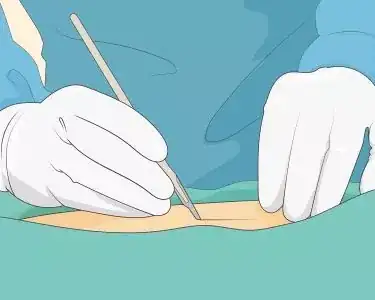

How to

Read a Lumbar MRI

Expert